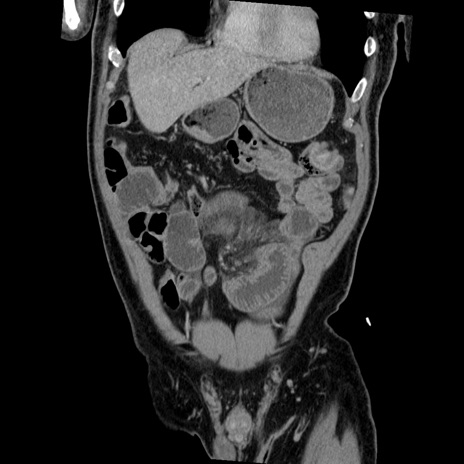

症例22(冠状断像)

【症例】50歳代男性

【主訴】腹痛

【現病歴】AVMからの被殻出血のため回復期リハ病棟入院中。 本日午後3時頃急に下腹部痛が出現した。

【既往歴】AVM、被殻出血、虫垂炎、高血圧

【身体所見】意識晴明、左半身不全麻痺、会話の理解は良好、36.5°C、腹部:膨隆、全体に板状硬、下腹部正中に圧痛点あり、反跳痛-、筋性防御不明、右下腹部にope scar

【データ】WBC 9400、CRP 0.06